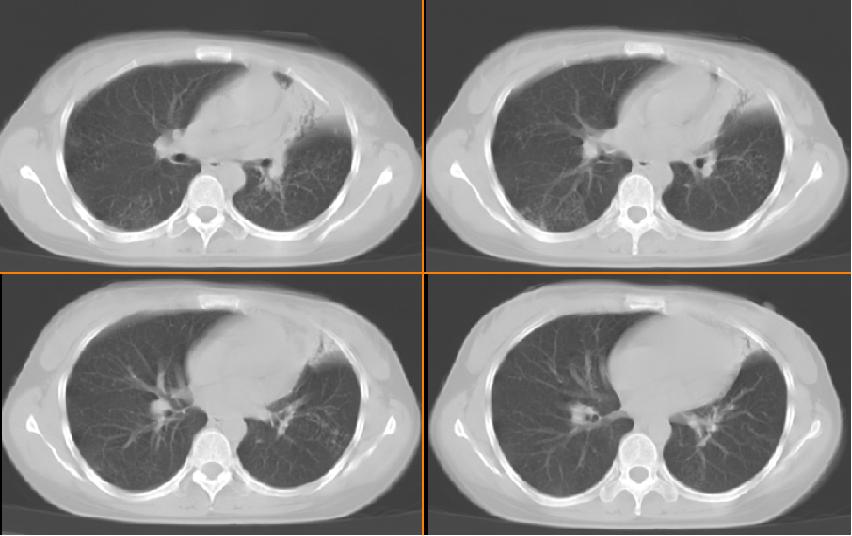

女,33岁,咳嗽5月。

左肺上叶前段致密,内见空气支气管征,相应部位胸膜增厚粘连,双肺上其他肺叶不同程度斑片状播散病灶,结合咳嗽5月的病史,考虑:双肺上叶继发性肺结核。

左肺上叶前段致密,内见空气支气管征,相应部位胸膜增厚粘连,双肺上其他肺叶不同程度斑片状播散病灶,结合咳嗽5月的病史,考虑:双肺上叶继发性肺结核伴左肺上叶肺含气不良。